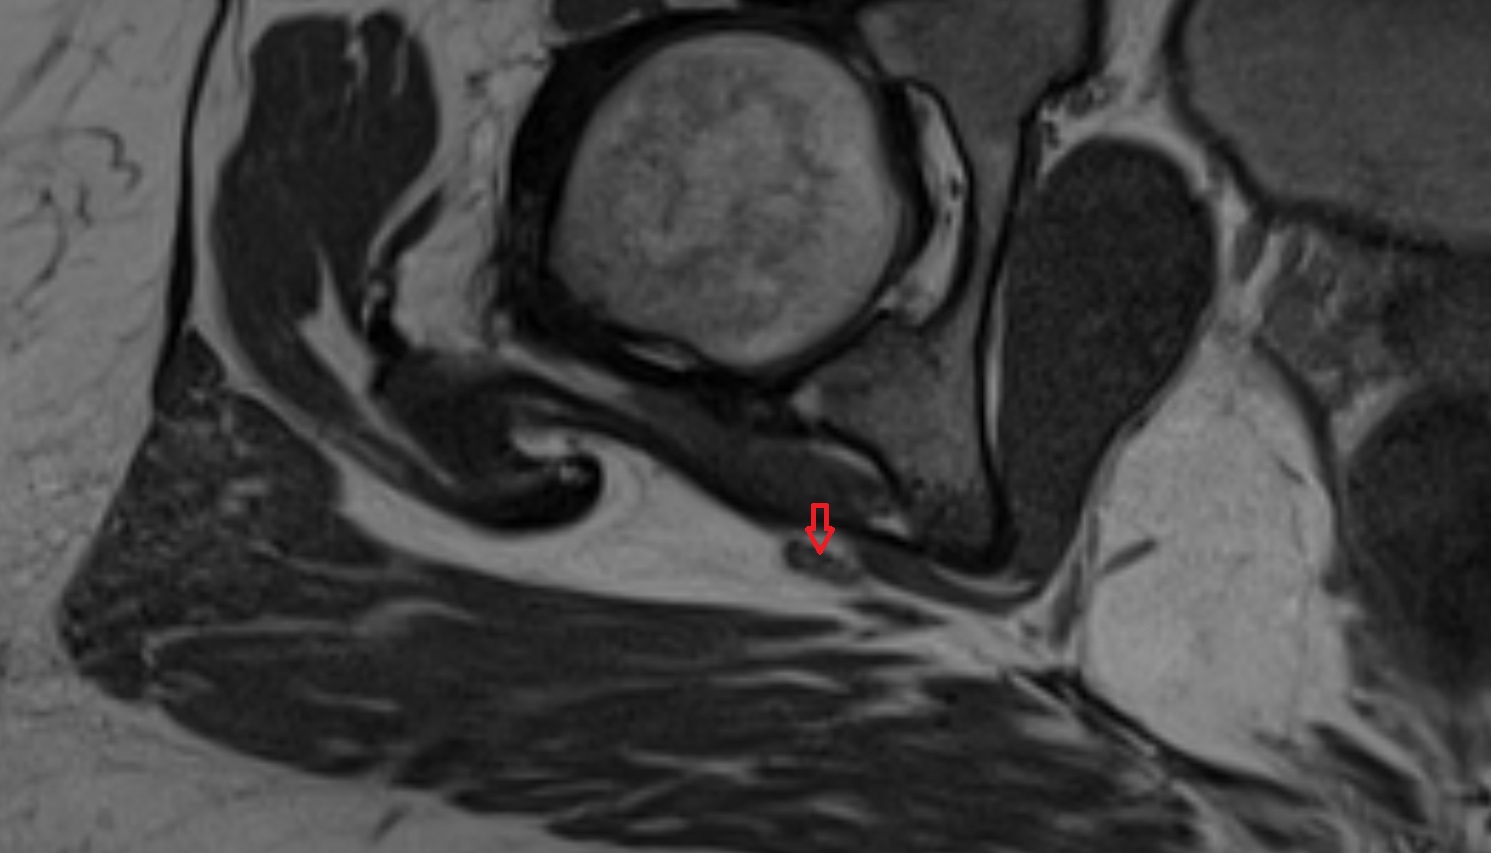

- Medial meniscus

- Lateral meniscus

- Posterior horn of medial meniscus

- Posterior horn of lateral meniscus